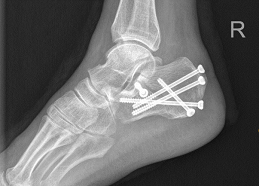

患者术前影像显示根骨粉碎性骨折